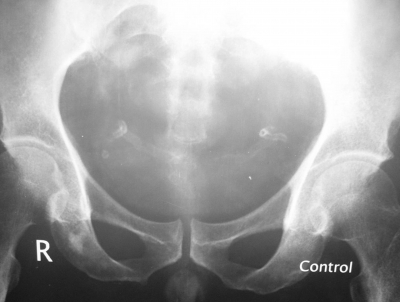

What is abnormal about this radiograph? What is the most likely comorbidity?

This patient manifests two tracklike calcifications symmetrically on each side of the bladder that end in the urethra – the vas deferens! This occurs much more commonly and earlier in diabetics than as a natural degenerative process.